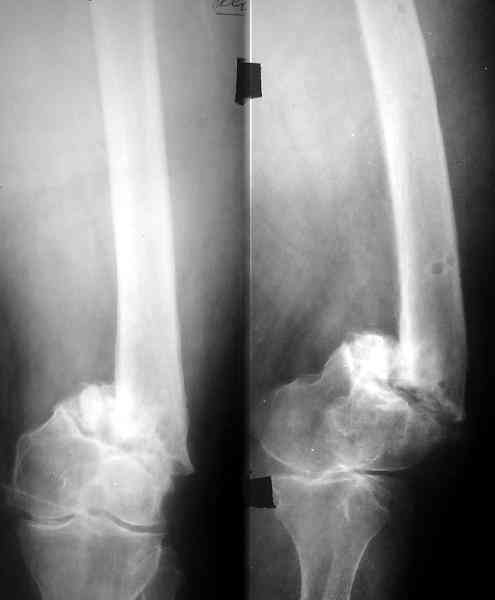

Доброго времени суток,уважаемые коллеги! Прошу вашего мнения. Больная, 53 лет,поступила с диагнозом: Ложный сустав н/3 бедренной кости слева. Травма в 1995г. Закрытый перелом н/3 левого бедра,лечение скелетным вытяжением. 15 лет ходила без трости. В 1-2010 года, рефрактура левого бедра в н/3. Лечение консервативное, скелетное вытяжение 2,5 месяца. Выписана в полужестком туторе. На ногу не опиралась, передвигается при помощи костылей. Инвалид 3 гр. посттромбофлебитический синдром левой нижней конечности. По дуплексному сканированию сосудов нижних конечностей вены проходимы, только на голени подкожная вена "посттромбофлебитическая".Из сопутствующих: ГБ,ДУЗ 0ст.Ожирение 1 ст.Предлагается костная пластика одним из существующих методов, накостный синтез мыщелковой пластиной LSP (Synthez). Укорочение левой ноги 3,5 см. Есть опасение, что накостный синтез ограничит периостальную регенерацию, да и травматичность операции при сопутствующих заболеваниях опасна в плане осложнений. Хотелось бы узнать мнение о ЧКДО и интрамедуллярном синтезе у данной пациентки. Стоит ли сначала "срастить" перелом, а потом коррегировать длину конечности? Или это нужно делать сразу? Может быть вообще ничего не делать и разрешить нагрузку? Пробую приложить Rn-гр. и томогр. Извиняюсь за качество обработки. Спасибо. Надеюсь на ваше понимание.

Смещение по длине см на 3 видно на снимке. Удобно и нетравматично восстановить длину и устранить смещение по ширине аппаратом.

По всей вероятности, после перелома бедренной кости, случившегося 15 лет назад, у больной сформировался псевдоартроз в дистальной эпиметафизарной зоне. Травма этого года привела, с моей точки зрения, к частичному разрушению псевдоартроза, а не к повторному перелому. Учитывая амнестические данные о больной, я бы не спешил с оперативным вмешательством, а предложил бы больной съёмный ортез и нагрузку на ногу в течение двух-трёх месяцев. Такой промежуток времени при данной патологии не ухудшит условия для оперативного вмешательства, если оно потребуется, но позволит более определённо установить необходимость такового, если конечность не станет опорной или больная сама станет настаивать на оперативном вмешательстве.

Что касается самого оперативного лечения, то оно представляет значительные трудности и положительный исход его не столь очевиден. С моей точки зрения, адекватная фиксация любой металлоконструкции в дистальном отломке бедренной кости невозможна. Поэтому вариантов вмешательства два: либо ВКДО с фиксацией голени (что, учитывая конституцию больной и сопутствующую патологию, менее приемлемо), либо антеградный БИОС с прохождением стержня через коленный сустав и дистальным блокированием в проксимальном эпиметафизе большеберцовой кости. И в том и другом случае потребуется открытая репозиция и костная пластика (возможно в несколько этапов). Вопросы восстановления длины конечности и функции коленного сустава на данном этапе лечения не главные. Цель оперативного лечения – восстановление опорной функции конечности и сращение перелома.

Пример подобного ложного сустава в приложении.